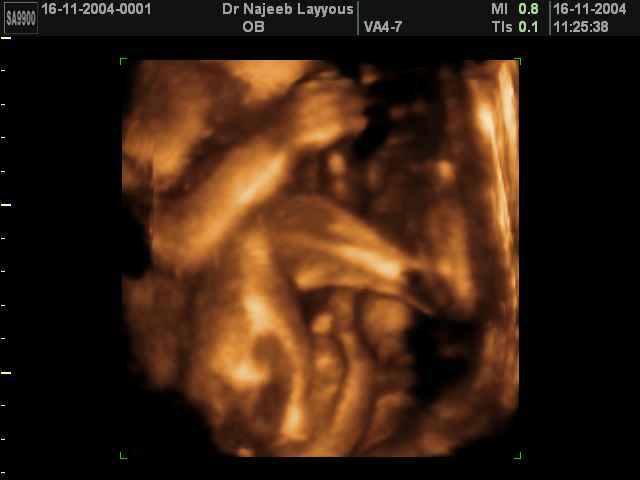

- 3D Photos échographie des parties du fœtus